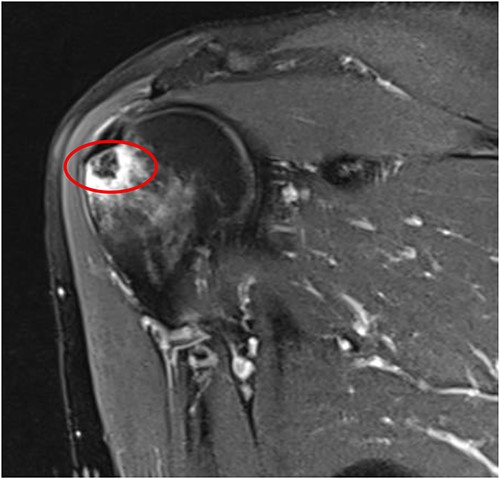

An MRI of the right shoulder showed calcifications over the supraspinatus tendon with an intraosseous lesion mimicking an aggressive or benign skeletal neoplasm (see Figs 2 and 3).

Coronal T2 image of right shoulder showing hypointense lesion; note: the red circle indicates the intraosseous extension of calcified deposits originating from calcified supraspinatus tendon, with surrounding marrow edema.